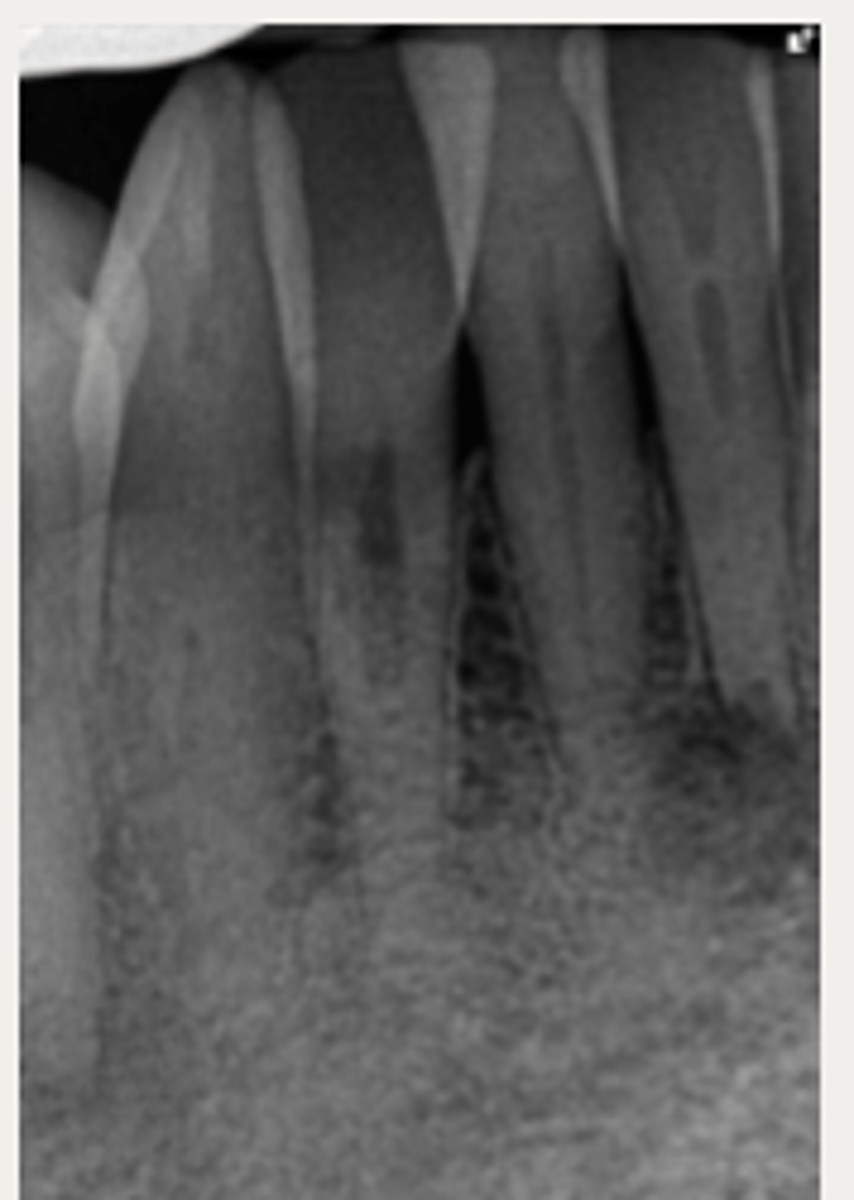

External Inflammatory Resorption (EIR)

Which type of resorption?

Lateral External Inflammatory Resorption

ID the type of resorption:

CLINICAL:

- History of trauma

- Pulpal Dx → necrotic

- Symptoms of apical periodontitis

- - May be tender to percussion and/or palpation

RADIOGRAPHIC:

- Radiolucent, crater shaped indentations on the root surface with adjacent bone loss and periradicular radiolucencies

Patient presents with history of trauma, does not respond to sensibility tests (necrotic pulp), is tender to percussion and/or palpation and has these radiographic findings. What is the most likely diagnosis?